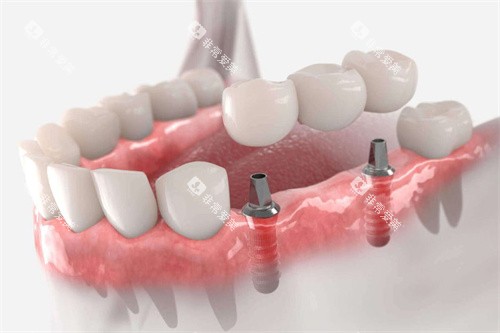

种植牙的质量特别大程度上取决于材料和工艺。

韩国登腾采用的是经过多年验证的钛合金材料,表面处理工艺成熟,能与人体牙槽骨较好地结合,成功概率较高。

而利多齿同样采用了优质的钛合金材料,并且在表面处理技术上不断创新。

经过正规机构的检测,利多齿在生物相容性方面表现出色,与牙槽骨的结合速度和稳定性并不逊色于韩国登腾。

在模拟口腔环境的测试中,两者的种植体在承受咀嚼压力等方面都能达到标准要求。